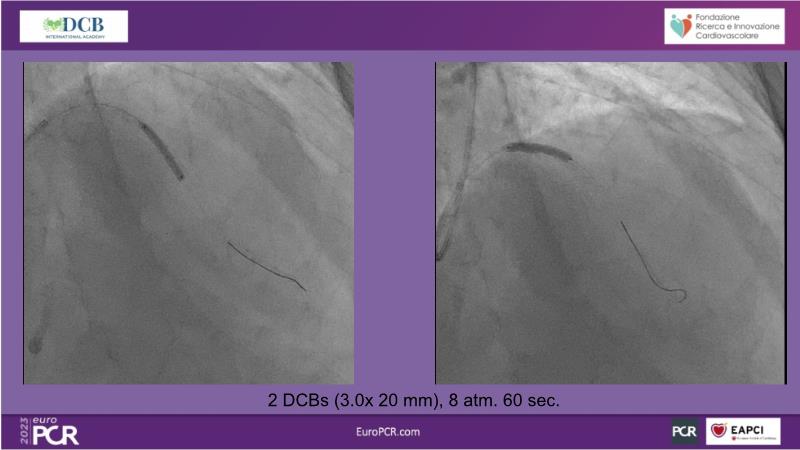

- To receive an in-depth insight into the latest clinical data and experiences on drug-coated balloon usage in in-stent restenosis, de-novo and bifurcation indications